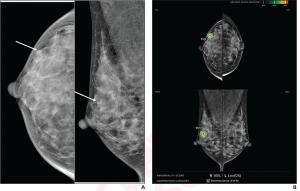

FDA Clears AI-Powered Triage Platform for Digital Breast Tomosynthesis